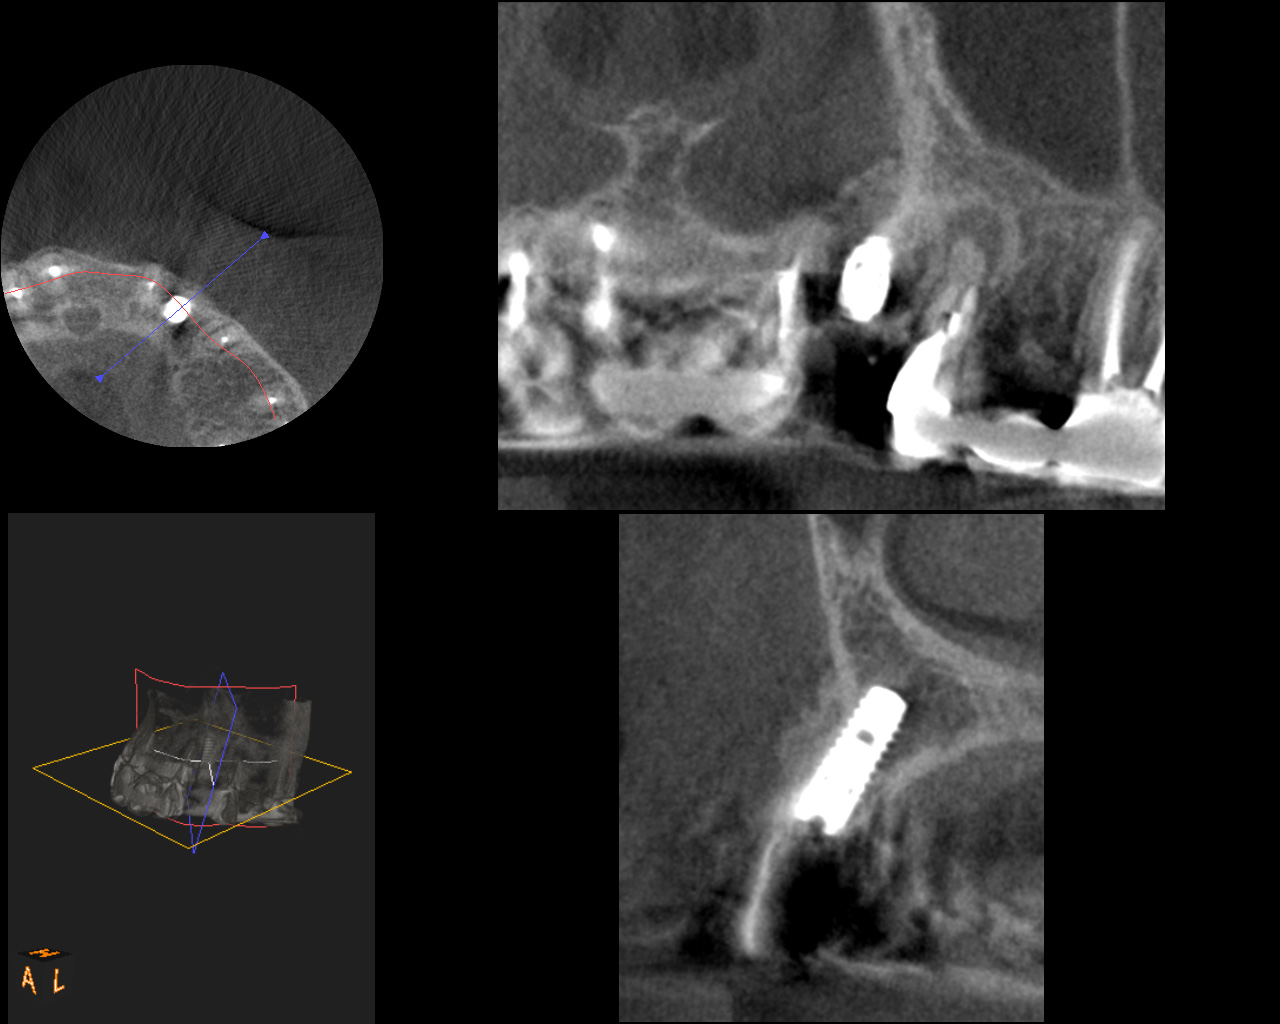

症例④

複数の歯に及び歯が失われているためCT画像上で診断と設計を行い、理想的な位置に歯を作ることができるように、サージカルガイドと言われるインプラント手術補助用マウスピースを用いてインプラント手術を行った。

術前CT

-

術後CT